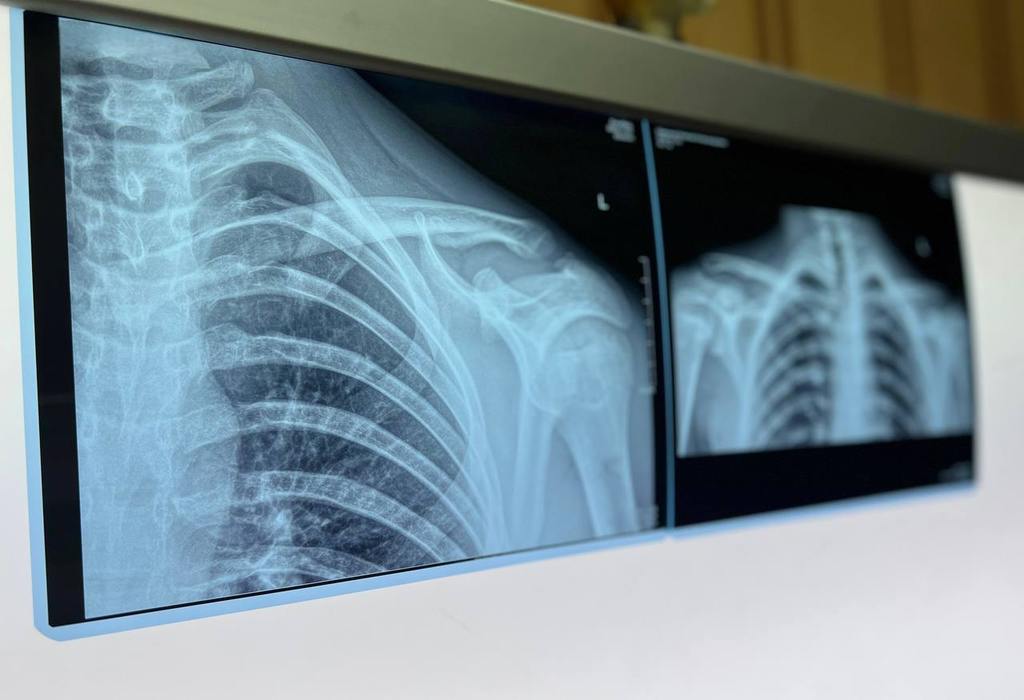

— Летом число детских травм значительно возрастает. В это время года дети больше проводят времени на улице. Они учатся ездить на велосипеде, качаются на качелях и рассекают на роликовых коньках. Все это приводит к нежелательным падениям, в результате которых дети чаще всего получают переломы предплечья, плечевой кости и костей голени, — прокомментировал Александр Григорьев главный врач МОДКТОБ, главный внештатный детский специалист травматолог-ортопед.